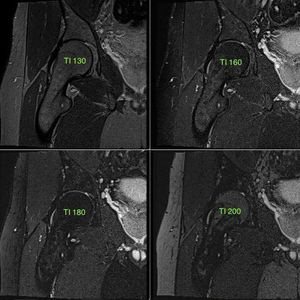

By modulating TI it is possible to adjust the strength of the desired fat suppression. The most powerfull fat suppression of the bone marrow is achieved with TI 180 ms (bottom left), which is close to the exact nulling time of the fat tissue. A lower (upper left & upper right) or higher (bottom right) TI will have weaker fat suppression. Image dataset acquired at 1.5 Tesla. ECR 2016 / C-0585 Fat Suppression Techniques for MR Imaging of the Musculoskeletal System